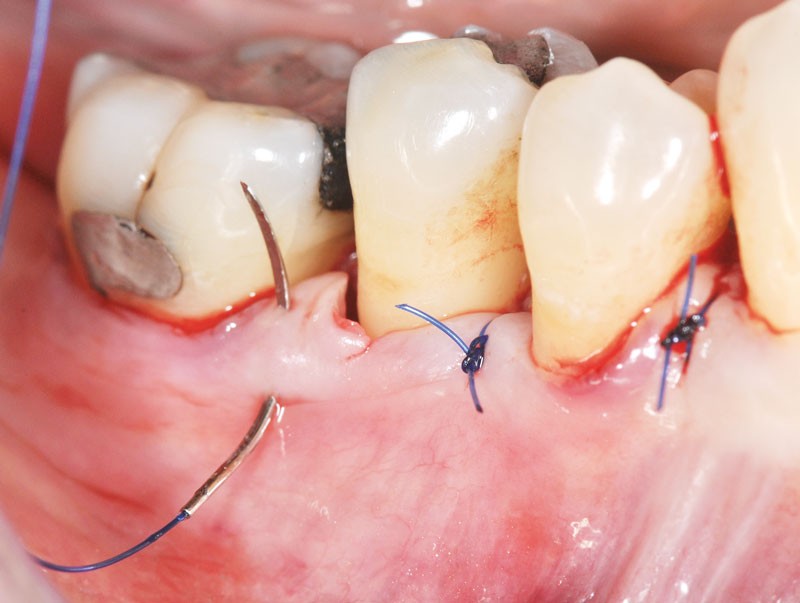

Greffes Libres Épithélio-Conjonctives

Type de cicatrisation : Cicatrisation par première intention avec contact direct entre le conjonctif de la greffe et le périoste.

La cicatrisation est décrite en trois phases critiques :

Phase 1 : Phase Initiale (0-48 heures)

Nutrition “plasmatique” :

Pendant les premières 48h, le tissu greffé est nourri par une circulation “plasmatique” provenant des vaisseaux sanguins du lit receveur et de ses berges.

Phase critique : C’est la phase la plus critique. Le greffon doit rester parfaitement immobile. Toute mobilisation peut compromettre la survie du greffon.

Conseil clinique : Pansement chirurgical et sutures hermétiques sont essentiels.

Phase 2 : Phase de Revascularisation (Jours 2 à 11)

2ème jour :

Des vaisseaux et des capillaires se forment à partir du lit receveur et réalisent un pontage (anastomoses) avec les vaisseaux existant dans le greffon.

Limite : Ce pontage n’est possible que si la zone avasculaire n’est pas trop large (importance d’un greffon pas trop épais).

4ème jour :

La circulation sanguine est presque établie normalement dans le greffon.

Un nouveau tissu conjonctif unit fermement la greffe au conjonctif sous-jacent.

7ème jour :

La ré-épithélialisation commence à partir de la périphérie du greffon.

Phase 3 : Phase de Maturation (Jours 11 à 42)

14ème jour :

L’épithélium se kératinise et les fibres de collagène s’orientent fonctionnellement selon les lignes de force.

21ème jour :

Le tissu épithélial est complètement mature avec toutes ses couches.

Jusqu’au 42ème jour :

Le tissu conjonctif continue sa maturation, augmentant progressivement sa résistance mécanique.

Stabilité : À partir de 6 semaines, la greffe est solidement intégrée.

Site Donneur (Palais)

Type de cicatrisation : La plaie se cicatrise par deuxième intention (détersion, bourgeonnement, contraction et épithélialisation).

Chronologie :

Périphérie de la plaie : L’épithélialisation débute à la périphérie

10 à 15 jours : La plaie est complètement recouverte par un nouvel épithélium

7 à 15 jours supplémentaires : L’épithélium mature dans toute son épaisseur

4 mois : Maturation tissulaire complète

Important : Si un second prélèvement doit être effectué sur le même site, il faut attendre la maturation tissulaire complète, obtenue à partir de 4 mois.